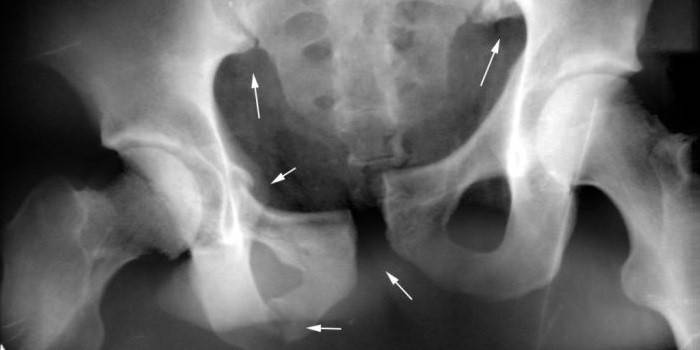

El íleon se encuentra en las partes superiores del hueso pélvico, forma parte del acetábulo y se considera emparejado. Este llamado soporte esquelético es el borde superior de la región ilíaca. El hueso ilíaco forma la sección pélvica del esqueleto humano y, si se desea, este elemento estructural se puede sentir mediante el método de palpación generalmente accesible.

Los segmentos derecho e izquierdo en ambos lados están unidos al sacro, estructuralmente tienen la parte superior redondeada. La parte inferior está notablemente engrosada y acortada, y en medicina se llama cuerpo del hueso ileal, que junto con los elementos púbico y ciático forman la parte superior del acetábulo. El fémur y el sacro están unidos al cuerpo.

En la parte superior del hueso del ilion hay una expansión, que solo forma el ala del ilion. Esta es una estructura más frágil. Su borde curvo externo se llama cresta ilíaca, tiene la forma de una protuberancia y debajo está la muesca ciática.La parte cóncava del ala forma la fosa ilíaca, la convexa forma la superficie de los glúteos, y en la región posterior en el interior está el sitio articular del sacro y el hueso pélvico, que se llama superficie en forma de oreja.